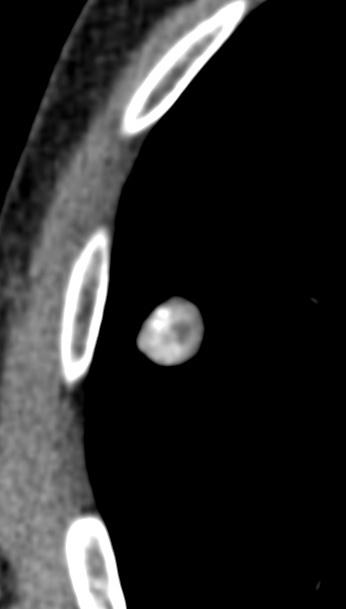

Radiology description

- Small coin lesion, often solitary, characterized by smooth edge, focal fat or fat alternating with calcific foci (Ann Thorac Med 2015;10:231)

- Calcifications often described as popcorn calcification

- Intralesional fat and popcorn-like calcifications allow a confident diagnosis on CT (J Thorac Imaging 2016;31:11)